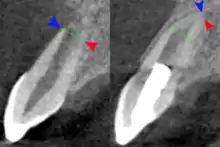

The secondary therapeutic goal of regenerative endodontic procedures is continued root development. A study has shown that teeth treated with revascularization showed a significantly greater percentage increase in root length compared with teeth treated by either mineral trioxide aggregate or calcium hydroxide apexification. Regenerative procedures promoted a decrease in apical diameter (apical closure). Root development allows the increase of the resistance to fracture and improve the tooth survival rate.[46]

Radiograph images, before and after the procedure are used to evaluate the outcome of the treatment. The patients are scheduled to follow up at 3, 6, 9, and 12 months after the completion of therapy. The tooth is accessed for different aspects such as pain, swelling, sinus tract, mobility, tooth discoloration, and the occlusion relationship. At the 12-month follow-up, CBCT images are taken to analyze the root development, in specific to access for the disappearance of apical radiolucency, increase of root length or a decrease of the apical foramen, or both.[51]